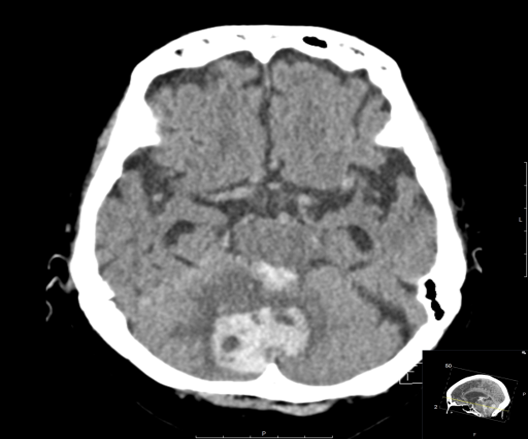

CASE 4 –An 82-year-old female of Asian descent from a nursing home presents with hypertension, nausea and vomiting. Vitals are BP 180/105, HR 65, GCS 8, which soon dropped to 6. Patient is K/C/O atrial fibrillation and is on warfarin. soon after arrival, warfarin was reversed due to suspicion of intracranial hemorrhage and the patient was sent for urgent CT scan.

EXPLANATION –There is a large intra-parenchymal hemorrhage located in the medial right cerebellar hemisphere extending into the cerebellar vermis. There is intraventricular extension into the fourth ventricle and aqueduct with mild obstructive hydrocephalus (mild dilatation of the lateral ventricles).

Cerebellar hemorrhage comprise approximately 10% of all intracerebral haemorrhages (ICH).

- Typical clinical symptoms are vertigo, ataxia, headache and vomiting. If they progress in size reduced consciousness will follow.

- Cerebellar hemorrhage may be related to hypertension, trauma, coagulopathy, hemorrhagic transformation of ischemic strokes, as well as underlying vascular abnormalities such as AVMs.

- Incidence increases with age and is most prevalent in Asian populations, as in our patient.

- Cerebellar bleeds are a neurosurgical emergency with urgent referral required due to the risk of mass effect and brain stem compression, cerebellar herniation and resultant hydrocephalus.

- This bleed was deemed nonsurvivable and the patient was managed on a palliative pathway. Amazingly, the next day she made a neurological recovery, she was obeying commands and ultimately returned to her nursing home.